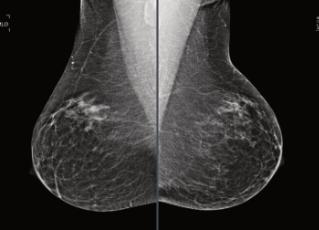

Laprevencióndelcáncermamarioenla mayoríadelosestudiosobservaciona‐leshademostradounaumentoenel riesgocuandosecombinanlosfactores convencionalesconelpatrónhereditarioo familiar.Esimportanteconocerelriesgoindi‐vidualdelaspacientesenlasevaluaciones periódicasporimagenyparadeterminarlose realizaunaencuestaacercadelahistoria familiardecáncerdemama,factoreshormo‐nalesyreproductivos,estilodeviday condicionesmamariasprevias.Estonos permitehacerunaevaluaciónintegralytomar accionesdirigidasquepuedanimpactarposi‐tivamenteenladeteccióntempranaylapre‐venciónprimaria.

Enapegoalasrecomendacionesrealizadas porelConsensoMexicanosobreeldiagnósti‐coytratamientodelcáncermamario2023,las recomendacionesgeneralesson:

•Eliniciodelautoexamenmamarioa partirdelos18años.

•Examenclínicoanualapartirdelos25años.

•Mastografíaanualdetamizajeenmujer asintomáticaapartirdelos40años.

•Lamastografíadedetecciónsumadaal ultrasonidoenmujeresconmamadensa aumentalasensibilidaddelaprimeratéc‐nicahastaun87%.

Retrasarladetecciónhastalos45o50añosre‐sultaenpérdidasinnecesariasdevida,afecta principalmentealasminoríasyalasmujeres enpaísessinunsistemaorganizadodetamiza‐jeparaelcáncerdemama.Iniciareltamizajea los40añostienevariosbeneficiosentrelos queseincluyen:reducciónenlamortalidaden un40%,diagnósticoenetapastempranas,me‐joresymayoresopcionesquirúrgicasy respuestaeficazalaquimioterapia.

Serecomiendaquelasmujeresdebende continuarconeltamizajeanualmientrasgo‐cendebuenasalud,yrealizarlobajolosestán‐daresdecalidadadecuadosquenosofrecela mastografíadigitalyelultrasonidoespecia‐lizado.Tomarencuentaelcontextoclínico,el riesgoindividualdecadapacienteysobre todonoperderlaperiodicidaddelas evaluacionesporimagenyaquesehademos‐tradoquelasumadelosmétodosdiagnós‐ticoscomolamastografíayultrasonidoau‐mentanlasensibilidaddelabúsqueda.